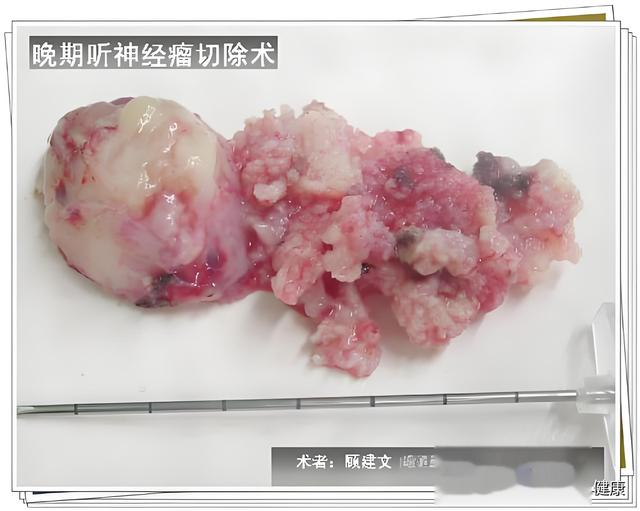

听神经瘤,又称前庭神经鞘瘤,起源于听神经鞘膜,是桥小脑角区最为常见的肿瘤,约占颅内肿瘤的 8%-10% 。其年发病率约为 1-2/10 万 ,且随着磁共振成像(MRI)技术的广泛应用,微小听神经瘤的检出率已提升至 65% 。手术切除目前仍是治疗听神经瘤的主要手段,其核心目标在于实现较高的肿瘤全切除率、良好的面神经解剖保留率以及一定比例的听力保留率。有研究表明,理想的手术效果应达到肿瘤全切除率>95% ,面神经解剖保留率>90% ,听力保留率达 30%-50% 。然而,由于听神经瘤所处位置毗邻众多重要的神经和血管结构,手术操作极具挑战性,因此不断探索和改进手术方法与技术具有至关重要的意义。本文将全面梳理听神经瘤手术方法的演变历程以及技术创新点。

该入路主要适用于肿瘤直径>2cm 且听力已丧失的患者 。对于此类患者,由于听力恢复的可能性极小,经迷路入路能够提供较为直接和广阔的手术视野,有利于肿瘤的完整切除。

大型肿瘤切除效果提升:对于大型肿瘤(>3cm),神经内镜辅助显微手术的切除率可提升至 98% 。神经内镜能够提供更广阔的视野,帮助术者观察到肿瘤与周围组织的复杂解剖关系,从而更彻底地切除肿瘤。例如,在对一组大型听神经瘤患者的手术治疗中,采用神经内镜辅助显微手术,肿瘤全切除率明显高于传统手术方式。减少术野死角:该技术能够有效减少术野死角,使手术视野更加清晰。研究表明,神经内镜辅助显微手术可使术野死角减少 67% ,有助于提高手术的精准性和安全性。在手术过程中,通过内镜的多角度观察,能够发现并处理传统显微镜下难以观察到的肿瘤残留组织和潜在的出血点。3.2.2 设备要求

大型肿瘤(>3cm)

经迷路入路 / 内镜辅助

94%

88%

对于内听道内肿瘤,颅中窝入路和耳内镜辅助手术能够提供良好的手术视野,有利于肿瘤的精准切除,全切率可达 97%,面神经保留率为 95% 。小型肿瘤(<2cm)由于其体积较小,乙状窦后入路在保留听力的同时,能够较好地实现肿瘤切除,全切率和面神经保留率分别为 96% 和 92% 。而对于大型肿瘤(>3cm),经迷路入路或内镜辅助手术能够更充分地暴露肿瘤,提高肿瘤切除的彻底性,全切率为 94%,面神经保留率为 88%